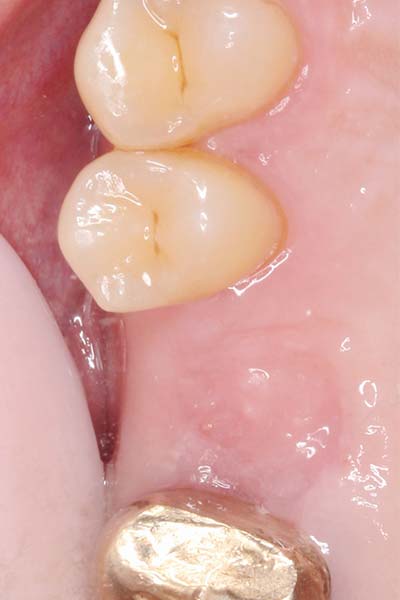

微創植牙 首頁 案例分享 人工植牙 微創植牙 微創植牙 牙周病的牙齒,因為骨頭破壞,只好拔除 拔牙後,置入骨粉,靜待骨頭癒合 晴美牙醫擁有豐富竹北微創植牙經驗,欲瞭解更多相關知識,可至診療項目-微創植牙頁面。 傷口癒合良好 微創不翻瓣 置入植牙 裝置假牙